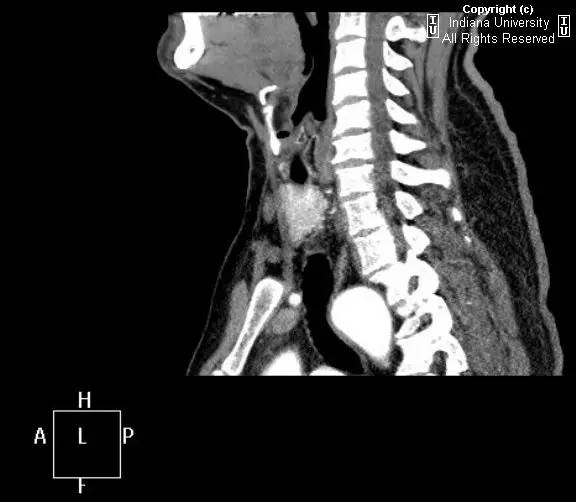

【影像学表现】胸部平片示右位主动脉弓,肺动脉突出,双肺清晰。CT示右位主动脉弓,并右位降主动脉,迷走左锁骨下动脉起自后方,从食管后走形形成血管环。迷走左锁骨下动脉与憩室相关(Kommerell)。食管因左锁骨下动脉及憩室而向前移位。

【诊断】右位主动脉弓并血管环形成、迷走左锁骨下动脉并Kommerell憩室

Right-sided aorticarch, with vascular ring and aberrant left subclavian with Kommerell\’sdiverticulum